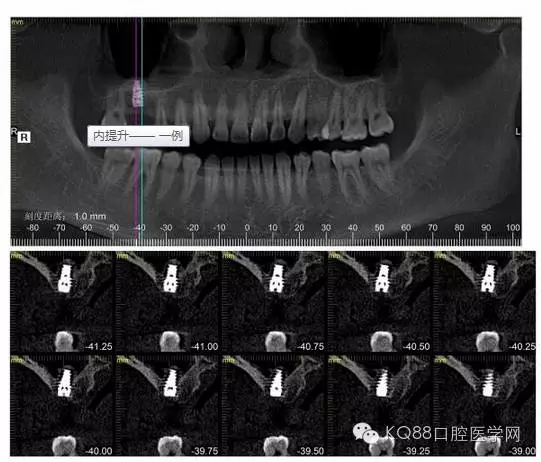

下面是拔牙后三個月的CBCT。垂直骨高度約6.7mm。

另外一個切面。垂直骨高度不夠,準(zhǔn)備 :做內(nèi)提升,植骨,植入植體。